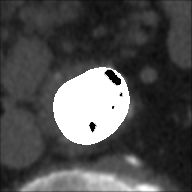

At this point, the dataset is ready for the processing in the portal ImageLab. The latter, takes as input the basal ROI and its corresponding CM one, together with their respective binary masks. These, are used by the algorithm to create the image (see Fig. 2), and consequently to detect the vessel. As depicted in Fig. 4, in output the extracted image is provided, along with a colored map where green highlights pixels correctly classified by the algorithm, red indicates misclassified ones, and white indicates the areas the algorithm should have identified but did not. Adjacent to this, similarity indices described before are presented, computed by considering the CM image as the target, which is provided as input for this purpose. We have processed in the portal each slice of our dataset.

In this version of the algorithm (updated compared to the one described in [30]), the calcium plaques are excluded from the patent lumen of the vessel and therefore visible in the processed image (in black), as we can observe also from Tables 3 and 4. The advantage of removing these structures during the extraction process leads to a more accurate and faithful evaluation of the indices. This observation is illustrated in Figure 6, where we present a comparison of results for a single slice obtained using the previous algorithm version, which does not remove calcium plaques from both the basal and the CM images, and the new algorithm version. The performance improvement is evident, particularly in the DCI index, where a difference is observed: of white pixels are accurately classified with the old version, compared to with the new version. Finally we highlight how, in the new version of the algorithm, the removal of the calcium plaques from both the basal and the CM images produces a different extraction of the patent lumen of the vessel, which in addition to being compatible with the algorithm’s steps, also turns out to be more accurate.

DCI: 0.894 | ||